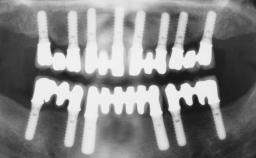

Conventional Loading of Eight Implants in the Maxilla and Final Restoration with a Full-Arch Gold-Ceramic FDP

A 35-year-old Caucasian female presenting with advanced periodontal disease involving both the maxillary and the mandibular dentition was referred for evaluation. The patient, a non-smoker in good general health, requested treatment for recurrent periodontal abscesses, tooth mobility, and discomfort during chewing, as well as restoration of her missing teeth with a fixed prosthesis to improve mastication and esthetics. All residual maxillary teeth exhibited plaque deposits, deep pockets, bleeding on probing, and class III mobility and were evaluated as hopeless. All residual mandibular teeth except tooth 37 could be maintained after periodontal therapy.

# of Implants 8

Type of Implants One-Piece

Bone Augmentation Horizontal|Staged|Vertical

Defining Characteristics Fully edentulous upper jaw to be rehabilitated with four or more implants

Bone Volume Deficient vertically or deficient vertically AND horizontally